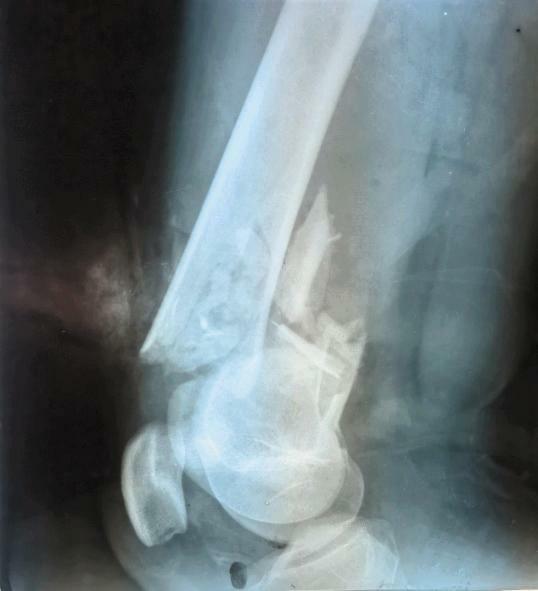

开放骨折最常见的原因是车祸,尤其是在交通工具相对落后、安全系数较差的苏丹,车祸致开放骨折患者非常多;最重要的是医疗设备落后及医疗环境差导致开放骨折致残率和截肢率极高。7月20日,余国勇大夫救治一严重开放骨折患者,入院时已13小时,出血多,患者已几乎处于休克状态,需抢救及行急诊手术,但要行手术需克服重重困难:1.受伤已超过6-8小时,伤口感染的风险极高;2.需输血,但血液需从首都送,最少需要4小时;3.无准备的骨折固定器械等。这里医疗条件落后,以往类似的患者都进行截肢了,但患者年轻,保全肢对患者来说极为重要,余国勇医生坚持克服种种困难为患者进行了保肢手术。经积极抢救,急诊手术顺利,患者生命体征平稳。

随后余国勇医生克服各种困难又为患者进行了两次手术,为患者得到了成功的救治并保全了肢体,此类手术的成功开展给当地患者的带来了福音,也扩大了中国医疗队的影响力。中国医疗队不远万里来到非洲苏丹这片热土上,用青春和汗水不断的去诠释和贯穿“不畏艰苦,甘于奉献,救死扶伤,大爱无疆”援外医疗精神。